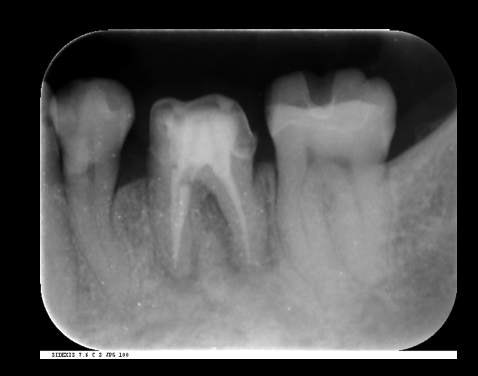

歯の根の治療(神経の治療)